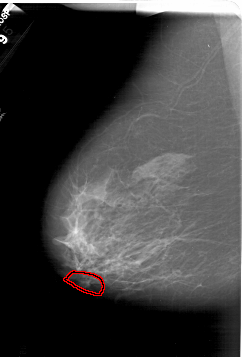

A_1386_1.LEFT_CC

LEFT_CC LINES 6841 PIXELS_PER_LINE 3976 BITS_PER_PIXEL 12 RESOLUTION 43.5 OVERLAY

FILE: A_1386_1.LEFT_CC.OVERLAY

TOTAL_ABNORMALITIES 1

ABNORMALITY 1

LESION_TYPE CALCIFICATION TYPE AMORPHOUS DISTRIBUTION LINEAR

ASSESSMENT 4

SUBTLETY 1

PATHOLOGY BENIGN

TOTAL_OUTLINES 1

BOUNDARY